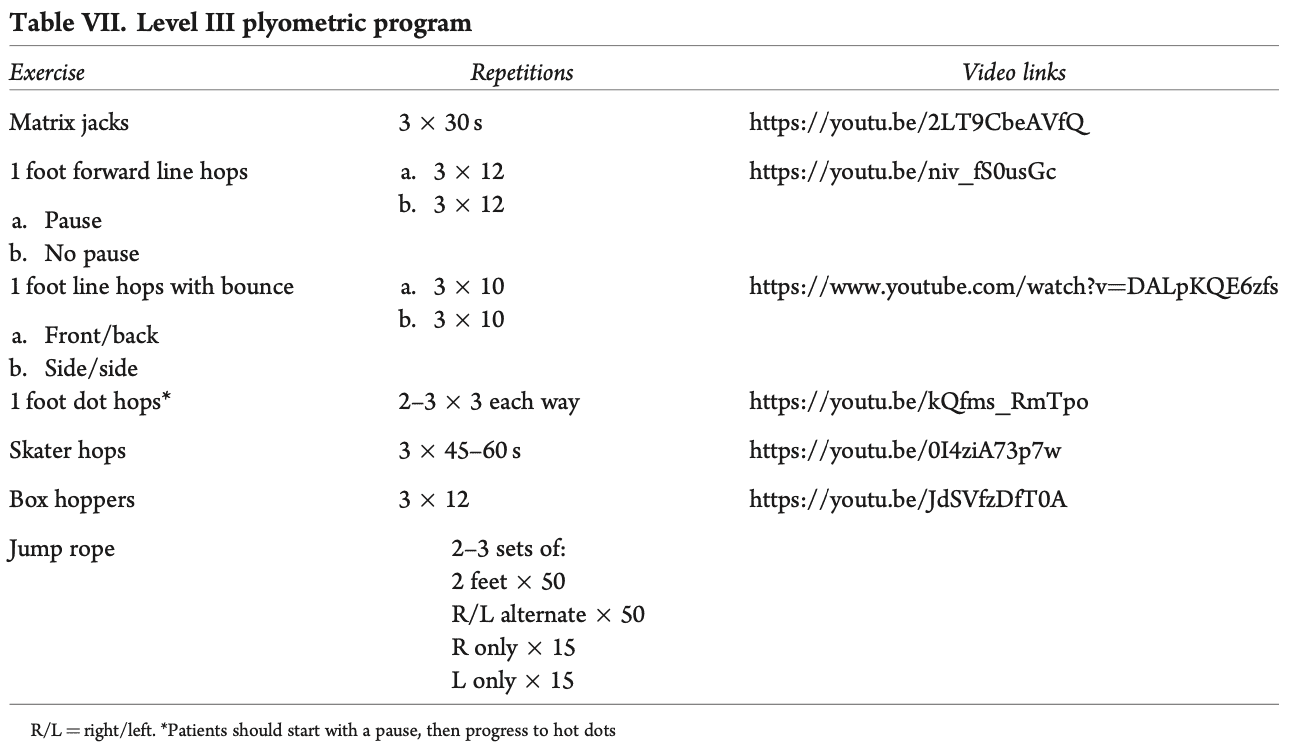

Oljaca 等人,2018 年对共识文件中有关 THA 后 RTS 的证据进行了分析,并总结如下表所示。 可以看到,在许多体育项目中,有关 RTS 的证据多年来一直在变化。

这个汇总表有话要说。 2022 年,本德测量了活体关节接触力和扭转力矩,发现保龄球等被认为是低冲击力的活动,与高冲击力的足球相比,会产生更高的关节接触力和扭转力矩。 此外,他们还发现体重和体重指数也会影响日常活动中的这些力。